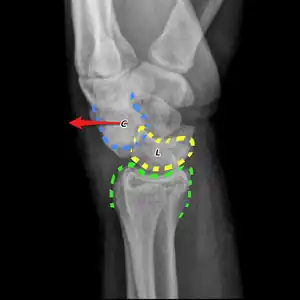

| A trans-scaphoid perilunate dislocation | |

The underlying cause generally involves significant trauma, with bending back of the wrist.[2] This may include a fall, motor vehicle collision, or sports injury.[1] Diagnosis is usually by X-rays.[2] Types include trans-scaphoid perilunate dislocation (60%); perilunate; trans-radial styloid; and trans-scaphoid trans-capitate perilunar.[2]